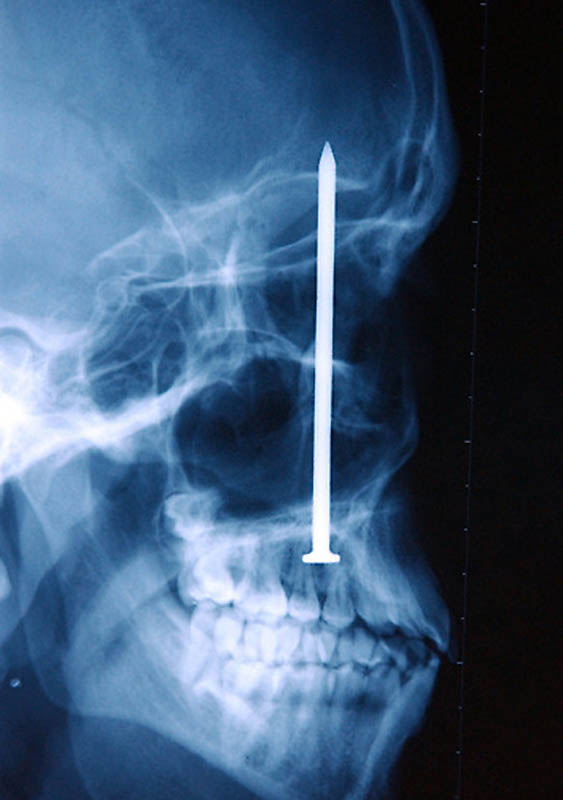

Гвоздь в человеческом черепе – пациент случайно выстрелил в себя из пневматического молотка. Он даже не понял, что выстрелил в себя – 10-сантиметровый гвоздь обнаружили только через 6 дней